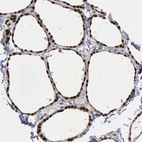

Immunohistochemistry analysis in human breast and skeletal muscle tissues using HPA001032 antibody. Corresponding PDCD4 RNA-seq data are presented for the same tissues.